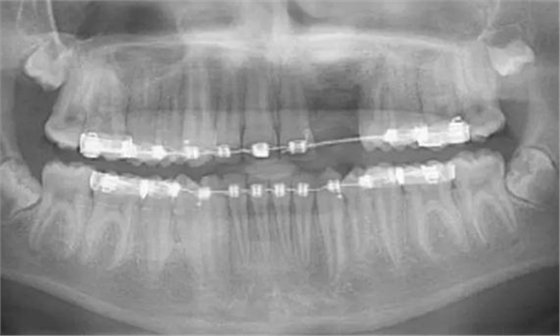

術(shù)后6個(gè)月的全景片表明生物性植入材料與天然骨組織之間實(shí)現(xiàn)完美平衡[圖5和6]

術(shù)后6年全景片中顯示手術(shù)已為將來種植打下了堅(jiān)實(shí)基礎(chǔ),在此病例中,如果將來進(jìn)行種植手術(shù),必須等到完全的骨愈合[圖7]